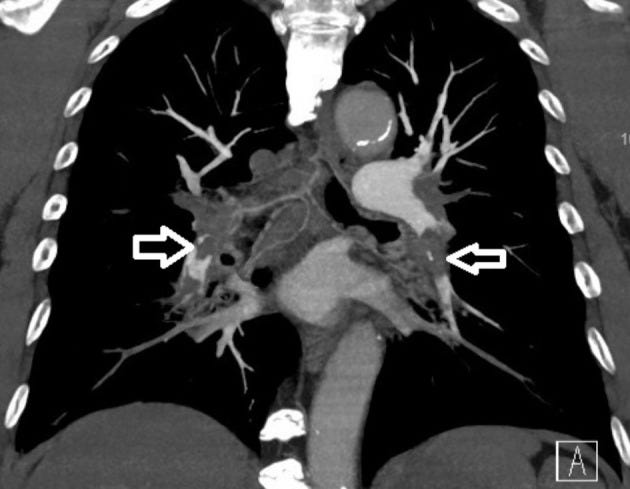

‘This case was a 70-year-old East Asian male, a current smoker, with a past medical history of hypertension and an old cerebrovascular accident, with independent activities of daily living. He received the first dose of the mRNA technology based Moderna mRNA-1273 vaccine 5 weeks prior to this episode.’ The patient presented to emergency department with ‘progressive shortness of breath for 5 days. A physical examination revealed blood pressure of 120/70 mmHg, heartbeat of 102 beats per min, and SpO2 around 90%. Resting 12-lead electrocardiography revealed sinus tachycardia and a typical S1Q3T3 pattern. Laboratory data showed normal platelet count, hemoglobin and fibrinogen levels. A SARS-CoV-2 polymerase chain reaction was negative. The D-dimer level was 4895 ng/mL, and chest computed tomography angiography showed bilateral saddle pulmonary embolism (Figure 1).

Bilateral pulmonary embolism noted on computed tomography angiography (white open arrows).